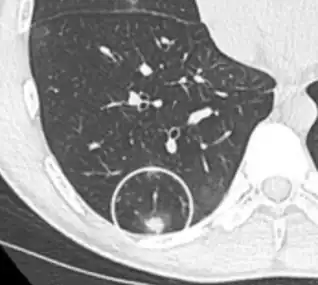

A "notch sign".[9]

A triangular perifissural node can be diagnosed as a benign lymph node.[9]